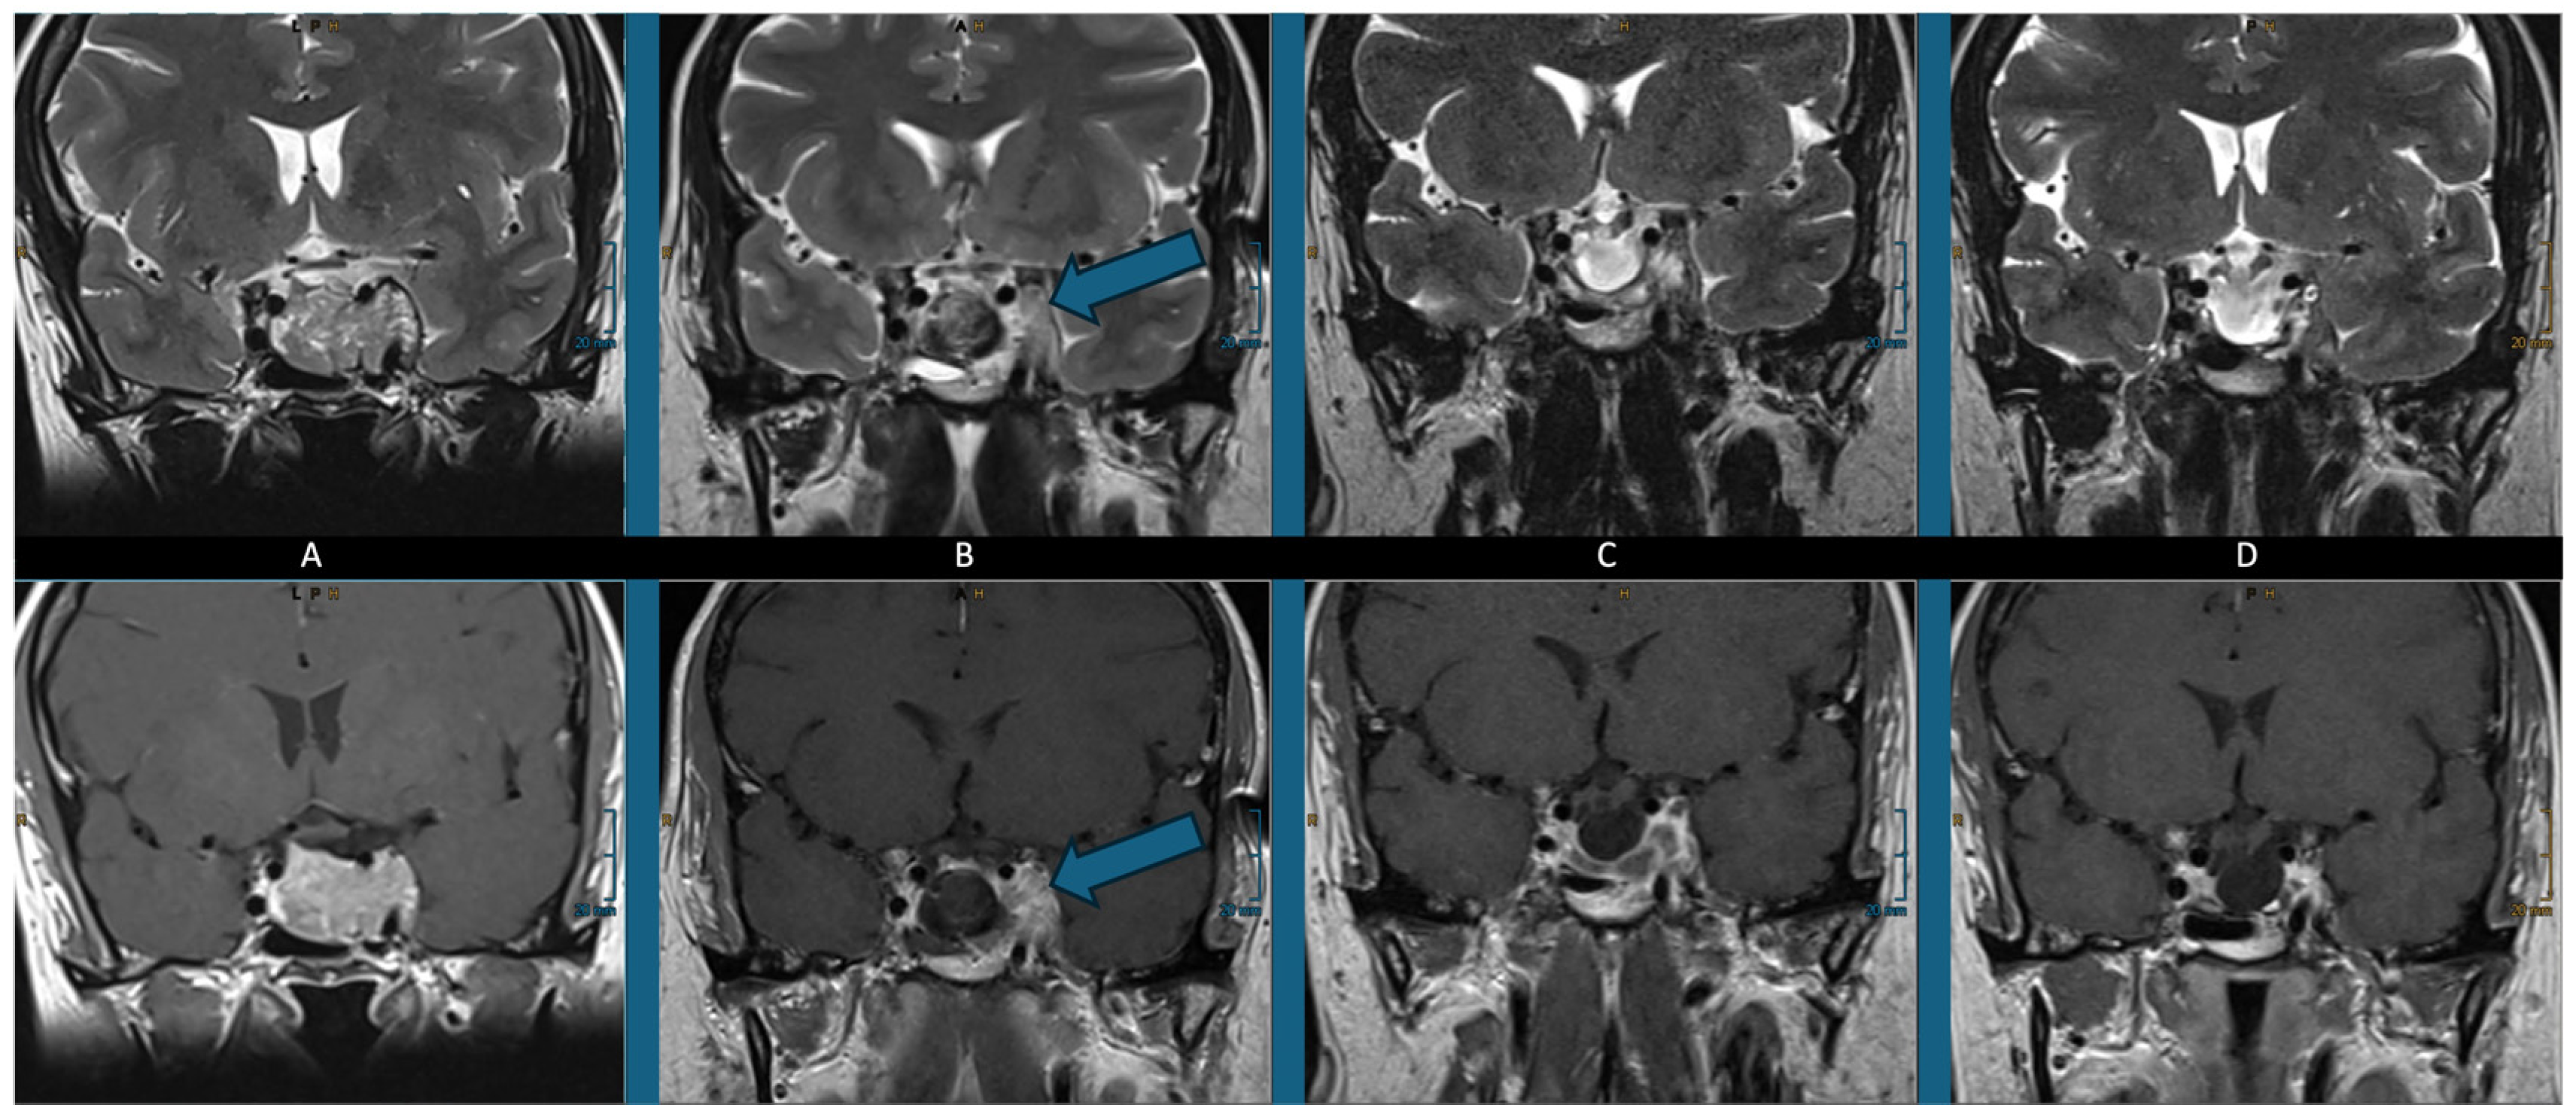

4. Illustrative Case